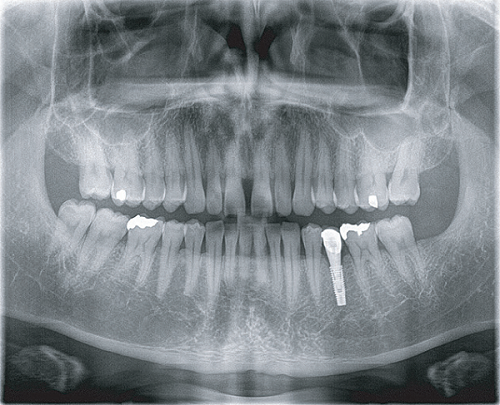

Apsaras 3D 口腔頜面錐形束計算機體層攝影設備

臨 床 圖 集